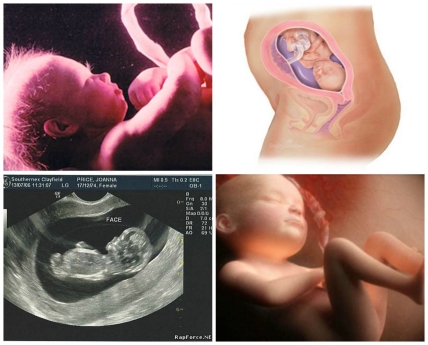

Развитие ребенка на 26-ой неделе беременности

26 неделя беременности: малыш продолжает активно набирать массу, к завершению этого срока его вес составит более 800 г. Присутствие собственного гормона роста приводит к быстрому увеличению длины плода, и в конце недели она достигнет 33-х см. Диаметр головки увеличится до 65,1 мм, грудной клетки – до 65,8 мм, а животика – до 67,4 мм.

Ребенок на 26 неделе беременности уже достаточно хорошо видит, ощущает пропорции и положение своего тела, способен различать вкусы и даже запахи. Плод хорошо слышит, причем, низкие звуки он различает и воспринимает лучше, чем высокие. Самым милым для ребенка звуком даже после рождения, остается звук биения материнского сердца, который он будет слушать все девять месяцев пребывания в животе.

На этой неделе развития заканчивается формирование глаз ребенка, поэтому он с легкостью может их открывать и закрывать. 26 неделя беременности обуславливается образованием у будущего малыша радужной оболочки глаз.

На 26 неделе беременности во рту ребенка продолжают закладываться зачатки постоянных зубов, также постепенно укрепляется костный аппарат, увеличивается мышечная масса. С развитием костной и мышечной массы ребенок начинает все активнее толкаться, строить гримасы, улыбаться и движением реагировать на позу маминого тела и вкус амниотических вод.

На этой неделе беременности у плода мужского пола яички уже чаще всего опустились в мошонку, но в некоторых случаях они задерживаются в брюшной полости и опускаются уже после рождения, в течение первых двух недель.